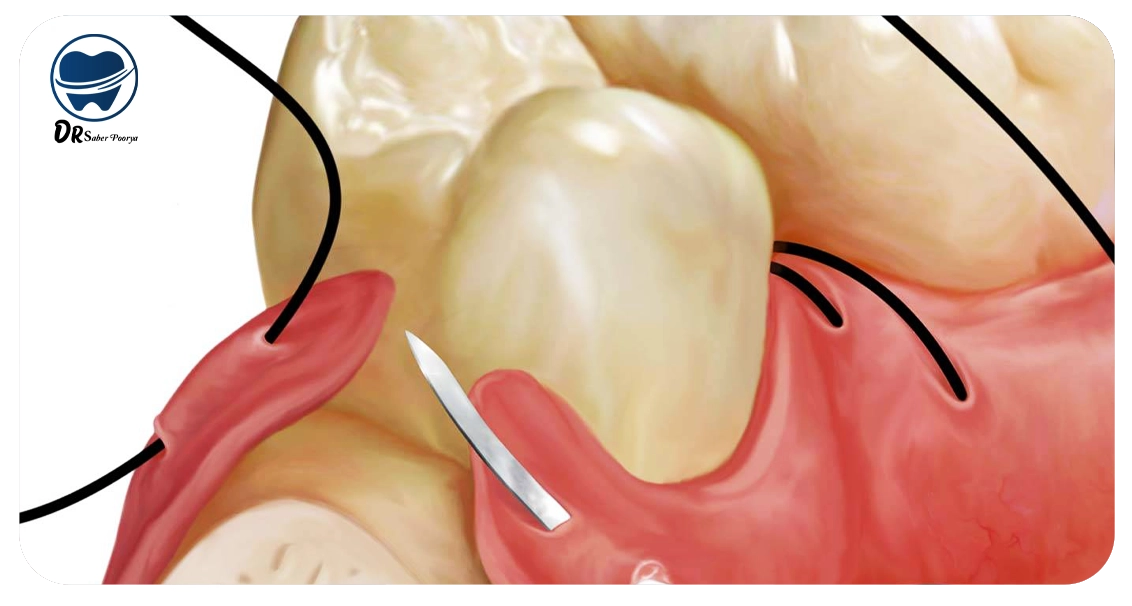

بخیه ایمپلنت دندان یکی از روشهای مؤثر جایگزینی دندانهای از دسترفته به شمار میرود. در این تکنیک، بهجای تراشیدن دندانهای مجاور، پایهای از جنس تیتانیوم درون استخوان فک قرار داده میشود.

جراحان برای دسترسی به بافت استخوان و ایجاد برشهای دقیق در لثه، از بخیههای باکیفیت و مقاوم استفاده میکنند تا روند ترمیم بافت سریعتر انجام شود.

فرآیند برداشت بخیههای ایمپلنت معمولاً ساده و بدون دردسر انجام میشود. دندانپزشک با دقت یکی از گرههای نخ را جدا کرده و سپس بخیه را بهآرامی از بافت لثه خارج میکند.

پس از برداشتن نخ، ممکن است بخش کوچکی از بافت دچار قرمزی یا زخم سطحی شود که نیاز به مراقبتهای محدود دارد. رعایت توصیههای دندانپزشک و تمیز نگهداشتن محل جراحی تا زمان ترمیم کامل، برای جلوگیری از التهاب یا عفونت اهمیت زیادی دارد.